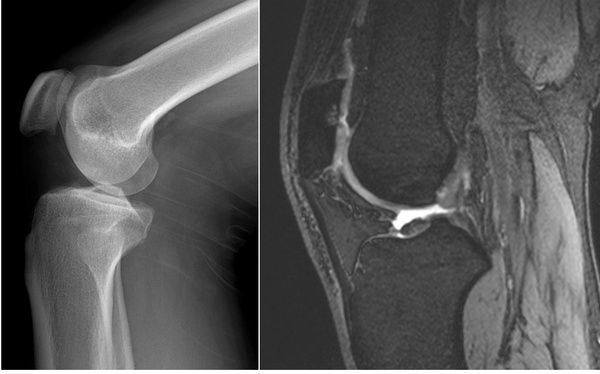

病例1:患者男,34岁,战士,因膝关节屈伸时弹响,下蹲困难1年做膝关节X线(上图左)及磁共振MRI(上图右)检查。X线检查提示未见明确骨质病变征象。但MRI-3D序列可见髌骨后缘局灶性骨髓水肿,相邻软骨变薄,提示髌骨软化症。

分析上两例患者情况,X线都没有观察到显著相关阳性改变,更难于发现膝关节软骨病变。但是,MRI均可以明确诊断为髌骨软化症。